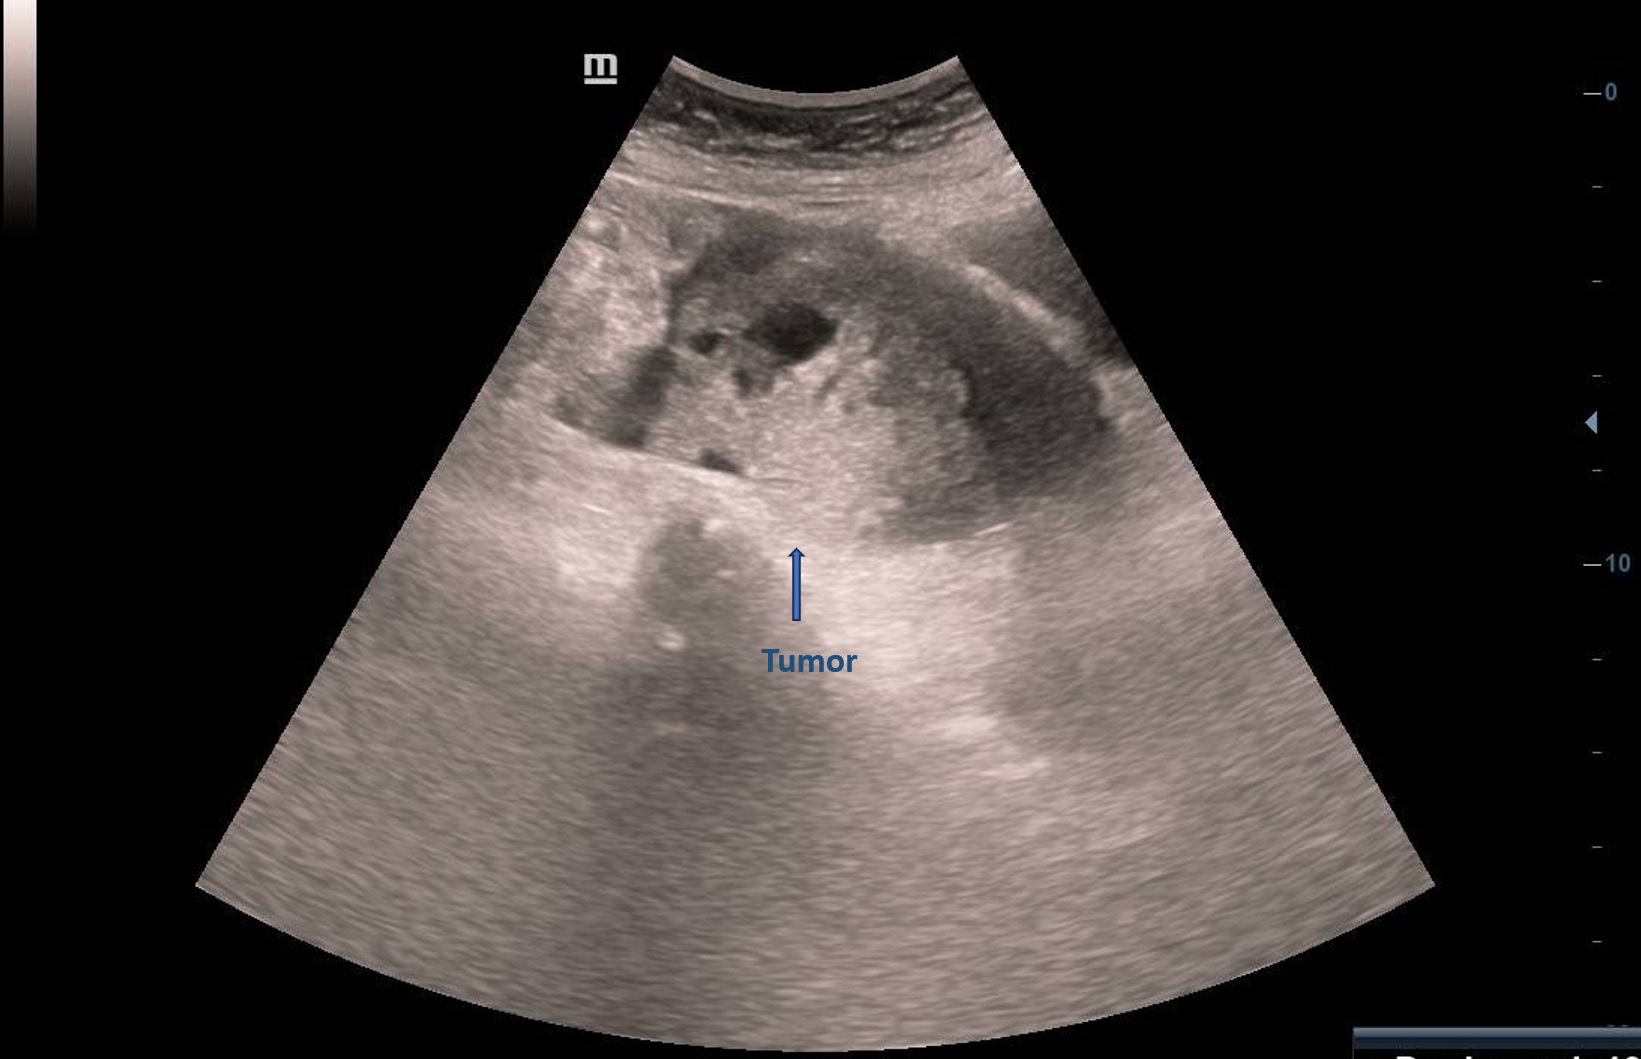

Ecografía abdominal en Atención Primaria: masa derecha adyacente a vejiga, vascularizada, de ecogenicidad heterogénea de unos 6 cm sin quedar clara dependencia del ovario derecho con imagen hipoecogénica en pelvis sugerente de ascitis. Se deriva paciente a ginecología preferente donde se realiza ecografía transvaginal: Tumoración anexial derecha, contorno irregular sugerente de neoplasia.

El EO se puede clasificar como benigno o maligno dependiendo de las características histológicas. En la ecografía aparece como una masa sólida heterogénea. No existen características ecográficas distintivas exclusivas. Ocasionalmente hay ascitis.